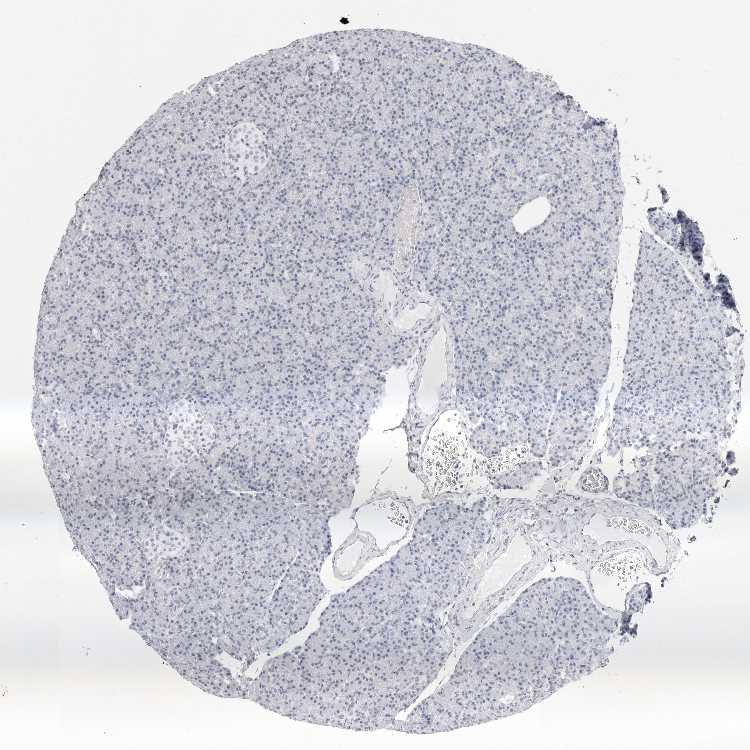

PANCREAS - Antibody stainingi

Antibody staining in the annotated cell types in the current human tissue is reported as not detected, low, medium, or high, based on conventional immunohistochemistry profiling in selected tissues. This score is based on the combination of the staining intensity and fraction of stained cells.

Each image is clickable and will lead to virtual microscopy that enables deeper exploration of all samples and also displays staining intensity scores, fraction scores and subcellular localization as well as patient and tissue information for each sample.

Antibody HPA028136Antibody HPA030518Antibody HPA030520

Exocrine glandular cells LowNot detectedLow

Pancreatic endocrine cells Not detectedNot detectedLow